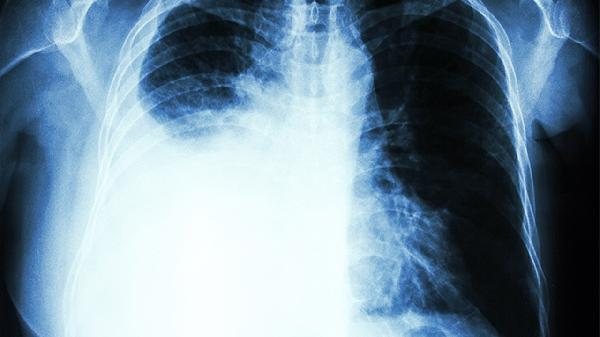

胸膜炎常由肺部感染蔓延所致,疼痛随呼吸运动加剧,可能伴有发热和咳嗽。需完善胸部CT检查,细菌性感染可遵医嘱使用头孢克肟分散片、左氧氟沙星片等抗生素。结核性胸膜炎需规范抗结核治疗,同时限制活动以减少胸膜摩擦。